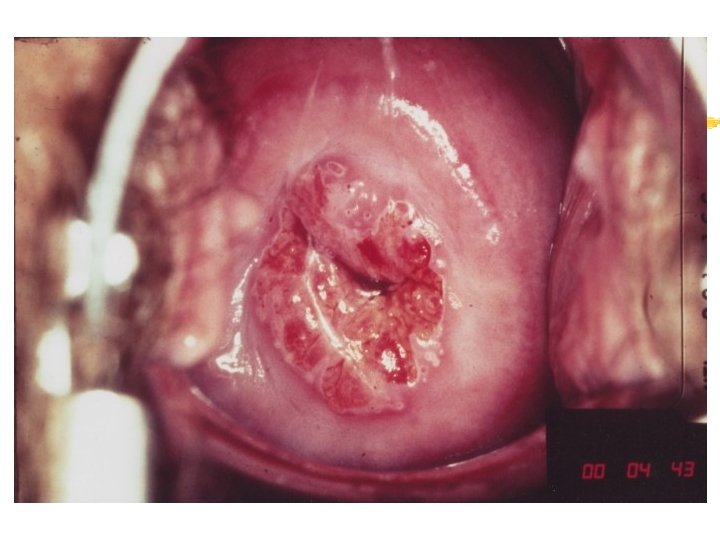

Warning signs of early cervical cancer 1. Yellowish and friable epithelium 2. Abnormal contour 3. Ulceration 4. Atypical vessels 5. Very severe colposcopic atypia 6. Large, significant lesion 7. Canal lesion, going out of range 8. Perimenopausal and post radiation

Mimics of cervical cancer 1. Severe cervicitis e. g. , herpes, syphilis 2. Benign ulceration e. g. , trauma 3. Foreign body reaction 4. Granulomatous cervical conditions 5. Granuloma inguinale 6. Lymphogranuloma venereum 7. Schistosomiasis 8. Cervical condylomata Cololposcopy aids differentiation. Histology is the gold standard

Cervicography: This is NOT Colposcopy High-quality colposcopic-type photography of the cervix Cervicoscope - Hand-held camera with a macrolens and a ring-flash Cervicogram - 35 -mm photo slide is taken Principles Recognition of lesions by means suitable magnification and illumination Fix up the problems of colposcopy 1. a less expensive form 2. noninvasive method 3. do not require expert skill

Procedures of cervicography A) Taking a 35 -mm cervicogram (1) Insert speculum and open as wide as possible … expose an entire cervix and upper vagina (2) Apply first application of 5% acetic acid by dabbing … cleanse the cervix of blood and mucus (3) View the cervix through the cervicoscope … allows time to begin taking epithelial change (4) Apply second application of acetic acid. (5) Take two cervicogram pictures B) Developing the images C) Interpreting a magnified image that was projected on the screen (1) Negative if no definitive lesions are visible (2) Atypical if there was evidence of acetowhite lesion of doubtful significance (3) Positive if there was evidence of a minor or major-grade lesion or cancer